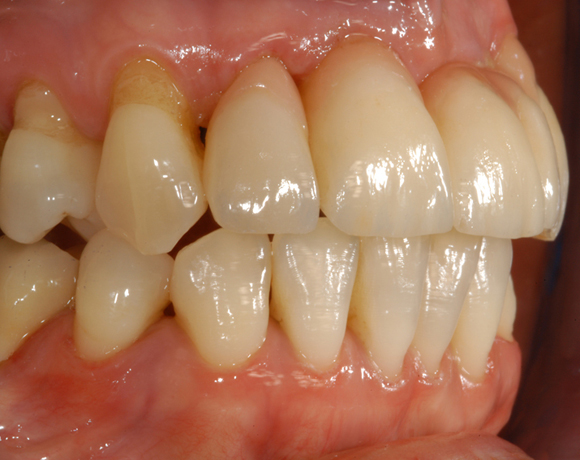

vollkeramischen Brücke versorgt. da die Patientin eine metallfreie Versorgung wünschte,

wurden Zeramex C Implantate gewählt, auch der Zahn 22 wurde mit einer vollkeramischen

Krone versorgt.